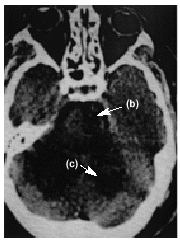

Figura 2.

En la figura 1 se aprecia hipodensidad en la región protuberancial izquierda y en hemisferios cerebelosos que comprimen la parte posterior de la cisterna protuberancial. En la figura 2 se observa una hiperdensidad en la salida de la arteria cerebral media (ACM) derecha (a) e hipodensidad de su territorio tributario, y en la figura 3 una hipodensidad de todo el territorio de la ACM derecha. Las flechas de la imagen delimitan la zona isquémica y señalan la hiperdensidad de la ACM, posición M1.

Diagnóstico: infarto de la protuberancia (b), cerebeloso (c) y del territorio de la ACM derecha (d) con visualización de la oclusión de la arteria tributaria de origen embólico.